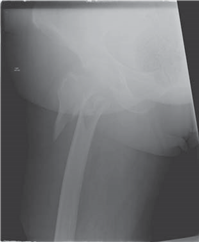

A 77-year-old woman fell off her bicycle sustaining this injury.

Illustration 5 for Ace Your FRCS: Key Questions in Trauma & Orthopaedics

What does this radiograph show and how would you classify this fracture?

There is a displaced intracapsular fracture of the right neck of femur. I would describe this as a Garden IV fracture as there is complete displacement. Clinically the most important classifi cation is simply between displaced and undisplaced fractures.

What would you like to like to know about the patient?

I need to know about any other injuries and the patientโ€™s acute medical status. I would then enquire about medical co-morbidities, residential status and her pre-morbid mobility. Her mental status both acutely and pre-injury are also important.

What is your initial management?

I would manage this patient along the recent British Orthopaedic Association Standards for Trauma (BOAST) guidelines. She requires analgesia, plain radiographs, and admission to an appropriate ward within 4 h. Routine bloods and electrocardiogram (ECG) are performed and the patient rehydrated. I would plan for surgery within 48 h unless a reversible medical condition was present.

How would you manage this patient?

A s mentioned earlier, I would follow the BOAST guidelines. I would discuss treatment with her and propose a total hip replacement (THR). Studies show that patients do better functionally with THR and re-operation rates are lower. I would certainly expect this particular patient to do better with THR. I would use a cemented cup and stem with a 32 mm head via a modifi ed Hardinge approach.

Although relatively uncommon, it is recommended that an orthogeriatrician should be involved in all phases of this patientโ€™s care.

How would you manage this fracture if it occurred in a 42-year-old?

I would aim to conserve the femoral head by reducing the fracture under direct visualization and fi xing internally with three screws.

This patient presented at 10 p.m. Would you operate that night?

I would operate the next morning as evidence suggests that rapid surgery does not aff ect outcome. The most important factor is accurate reduction.